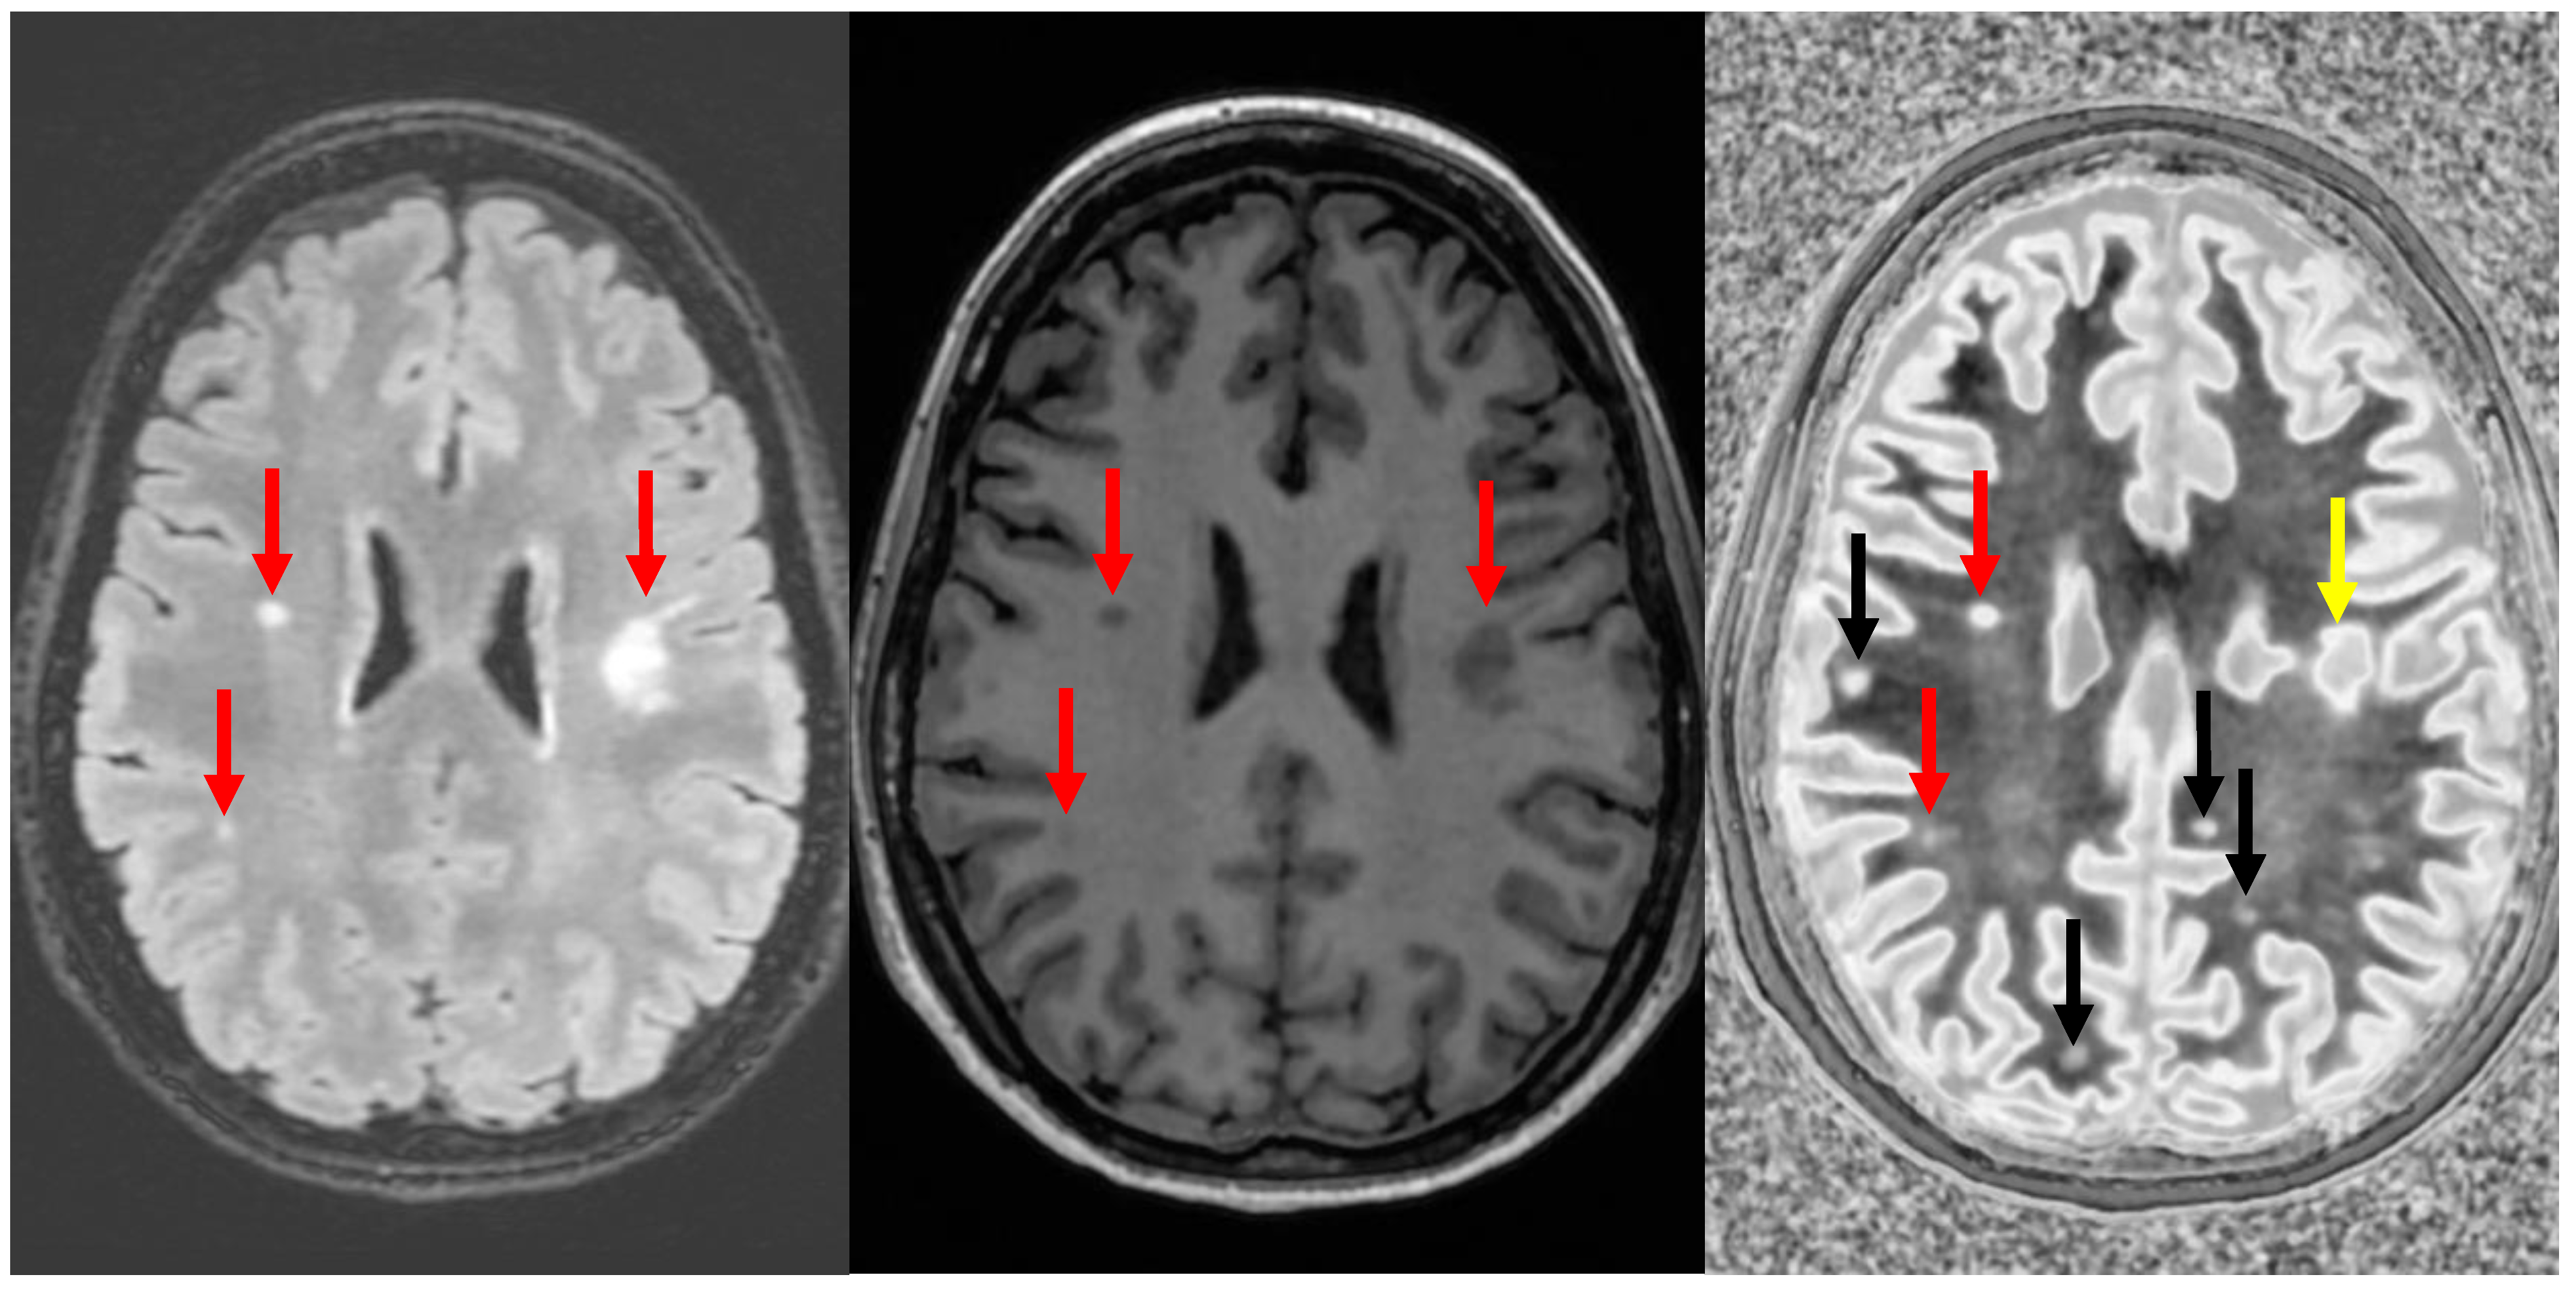

However, MS is a systemic disease of the white matter. Imaging early and potentially reversible changes in the white matter using dSIR could potentially change the way MS is imaged. In one MS patient having an acute decompensation, the narrow mD dSIR images show geographic, as opposed to focal, changes in the white matter (Figure 13). We do not have a longitudinal follow-up, nor do we have sufficient patients at our institution to perform a longitudinal study. However, collaborators at larger institutions are planning to study this.

Figure 13.

Divided Subtracted Inversion Recovery (dSIR) in a patient with multiple sclerosis (MS). Three axial narrow middle domain images in a patient with an acute MS flare at the level of the centrum semiovale (left), corona radiata (middle), and basal ganglia (right). TIshort = 350 ms. TIlong = 500 ms. TE = 7 ms, TR = 5000 ms. The white matter is not black as in Figure 9b. There is a widespread increased signal, though not a “white out” sign as described in Figure 14. This is an “intermediate” appearance but not considered normal.

Particularly encouraging, however, is anecdotal evidence that generalized white matter changes detected with dSIR sequences are reversible. Imaging in a patient following chronic methamphetamine use showed widespread white matter changes, which resolved following a prolonged period of abstinence (Figure 18). A similar reversibility was seen in a symptomatic patient following an mTBI (Figure 19). Imaging in the days following injury showed diffuse white matter changes which, along with the symptoms, resolved within two weeks.

Figure 18.

Divided Subtracted Inversion Recovery (dSIR) in a patient methamphetamine user. Narrow middle domain dSIR images at the level of the centrum semiovale (left), corona radiata (middle), and basal ganglia (right) in a volunteer immediately after a methamphetamine binge (top row) and 4 months into abstinence (bottom row) TIshort = 350 ms. TIlong = 500 ms. TE = 7 ms, TR = 5000 ms. The top row images show the “white out” sign, indicating diffuse mild white matter T1 elevation. The signal in the white matter partially normalizes on the bottom row. The appearance is closer to intermediate than normal, but there is definite improvement.

Figure 19.

Divided Subtracted Inversion Recovery (dSIR) in a patient with a mild traumatic brain injury. Narrow middle domain dSIR images at the level of the centrum semiovale (left), corona radiata (middle), and basal ganglia (right) in a volunteer within five days of an mTBI (top row) and two weeks later (bottom row). TIshort = 350 ms. TIlong = 500 ms. TE = 7 ms, TR = 5000 ms. The top row images show the “white out” sign, indicating diffuse mild white matter T1 elevation. The signal in the white matter normalizes on the bottom row, where it appears normal.